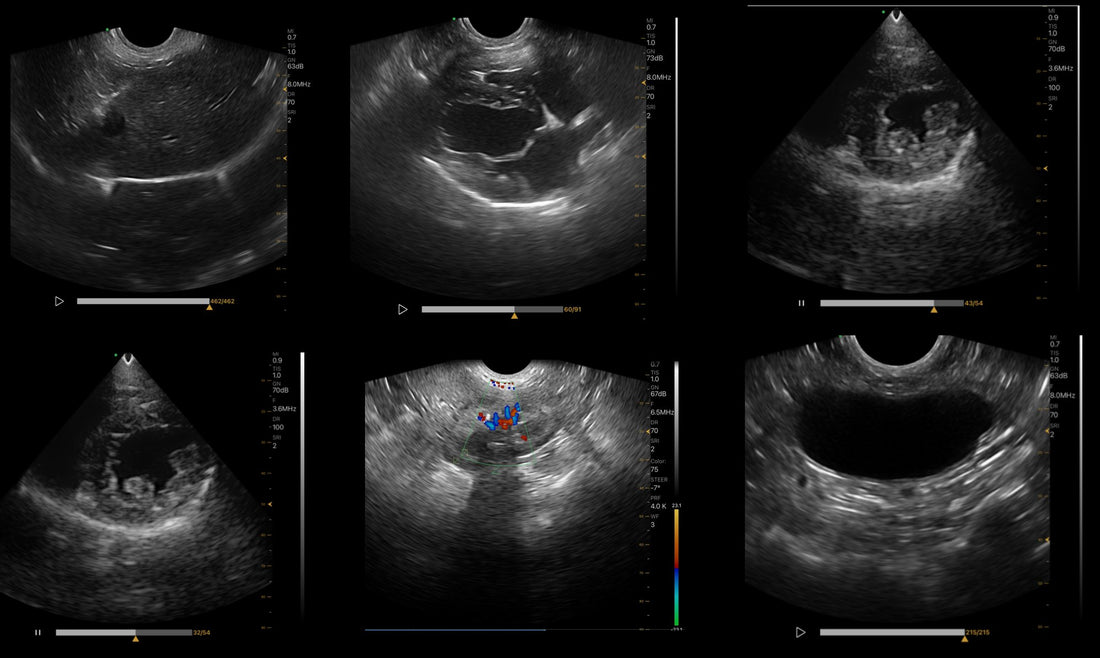

Canine abdominal ultrasound provides a detailed view of the organs and structures within the abdomen. It is a non-invasive diagnostic tool that veterinarians use to evaluate a variety of conditions and monitor ongoing health problems. Below is some of the important information that an abdominal ultrasound can reveal:

Kidneys: Size, shape, texture, presence of stones, cysts or abnormal structures.

Bladder: Bladder wall thickness, presence of stones, masses or abnormal contents.

Reproductive Organs: Uterus and ovaries in females, prostate and testes in males.

Fluid accumulation: Detect the presence of free fluid in the abdomen (ascites).

Vascular Abnormalities: Evaluate blood flow and identify problems such as portal vein shunts.